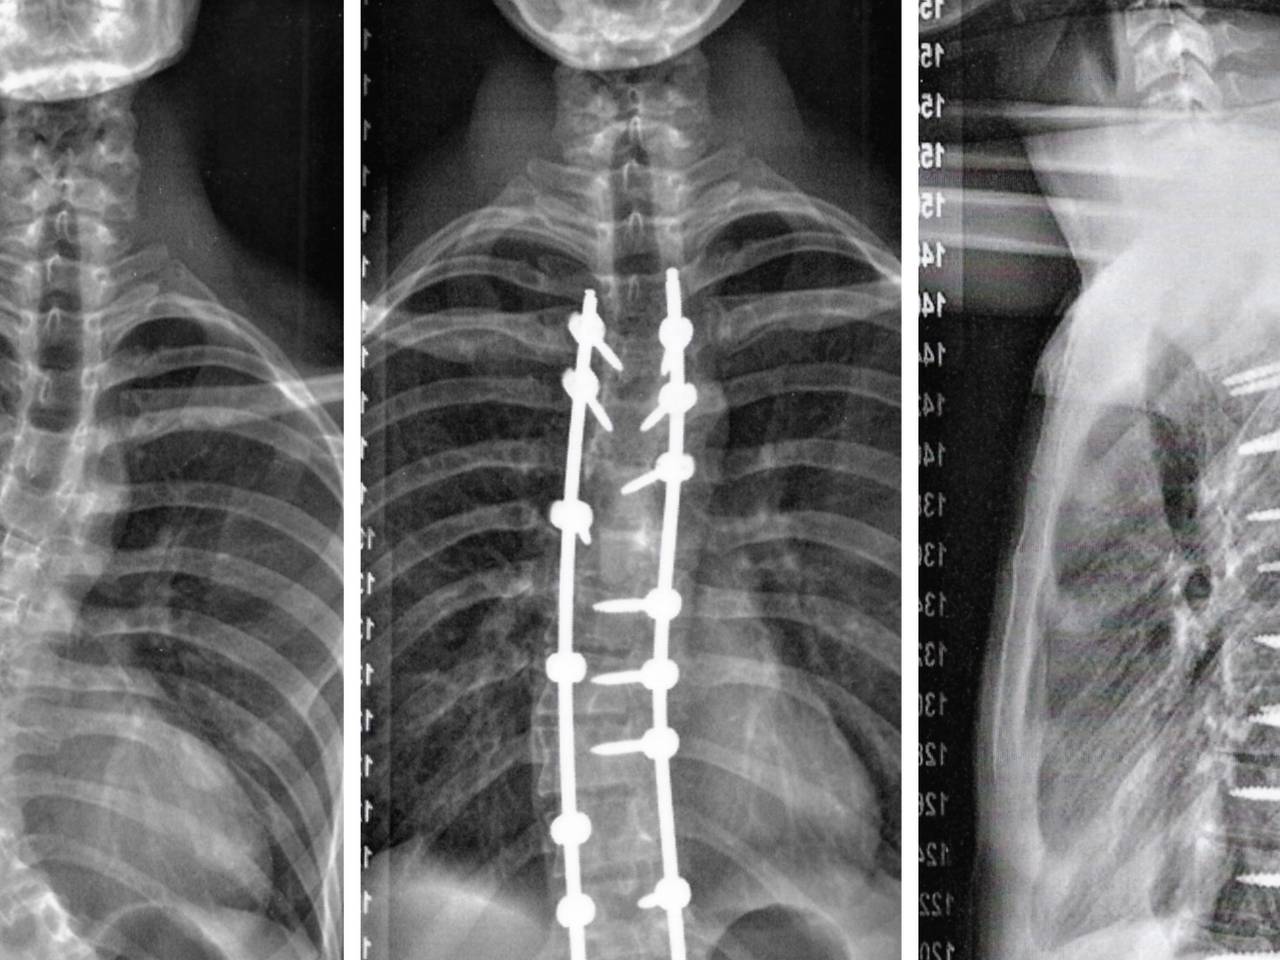

Toen hij vijftien jaar was, schoot Max de lucht in. "Dat was ook het moment dat mijn kromme rug opgemerkt werd door mijn ouders en klasgenoten op school in Oss. Die kromme rug heet scoliose. Het komt best vaak voor, bij drie op de honderd kinderen. Toch hebben maar weinig mensen ervan gehoord" , legt Max uit.

Fysiotherapie, revalidatie, voorkwamen niet dat hij toch onder het mes moest. "Voor een korset was ik te laat. Voor een operatie op mijn 16e te jong. Een jaar geleden ben ik geopereerd in Boxmeer. In de Sint Maartenskliniek zijn ze gespecialiseerd in scoliose. Er zitten nu schroeven en staven in mijn rug en ik heb een litteken van onderkant van mijn nek tot net boven mijn onderbroek als aandenken."